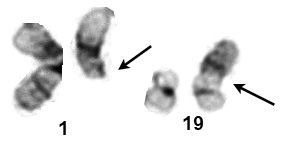

| Abnormal chromosome is on the right in each pair |

t(1;19)(q23;p13.3) | ALL | PBX1 TCF3 (E2A) |